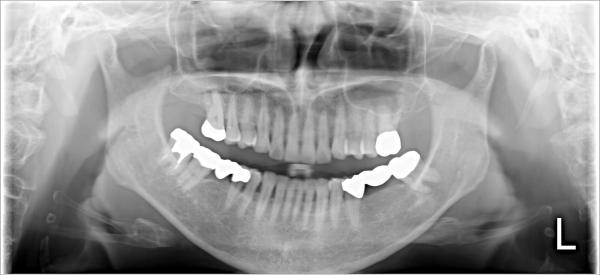

根管治療

治療の際に根管内に菌が残ってしまうと、歯を支える骨へと感染が広がってしまい、歯の根の先が膿んだり腫れや痛みを生じる場合があります。

そのため、根管治療では根管内の感染した部分をキレイに取り除き、根管内を無菌的にすることがとても重要です。

根管は非常に複雑な形をしており、形態や本数も人によって異なるため、根管治療は高い精度が求められる治療と言えます。当院では、ドクターの高い技術と先進の医療機器を駆使することで、より精度の高い根管治療をご提供しております。